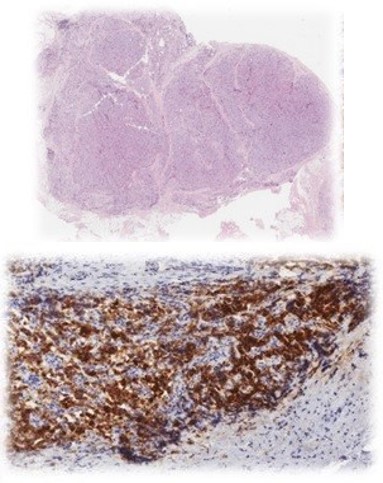

Cervical ultrasound, 18F-choline PET-CT, and 99mTc-sestamibi scintigraphy identified a hyperfunctioning parathyroid lesion (6×4 cm) in the left thyroid lobe, extending into the retroesophageal space, mediastinum, and thoracic vertebra T3. Suspecting parathyroid carcinoma, en bloc resection was performed, including four anterior and posterior mediastinal lymph nodes. Sternotomy was required for complete excision.

Figure 4: PET-CT with 18F-Choline: hyperfunctioning parathyroidlesión.